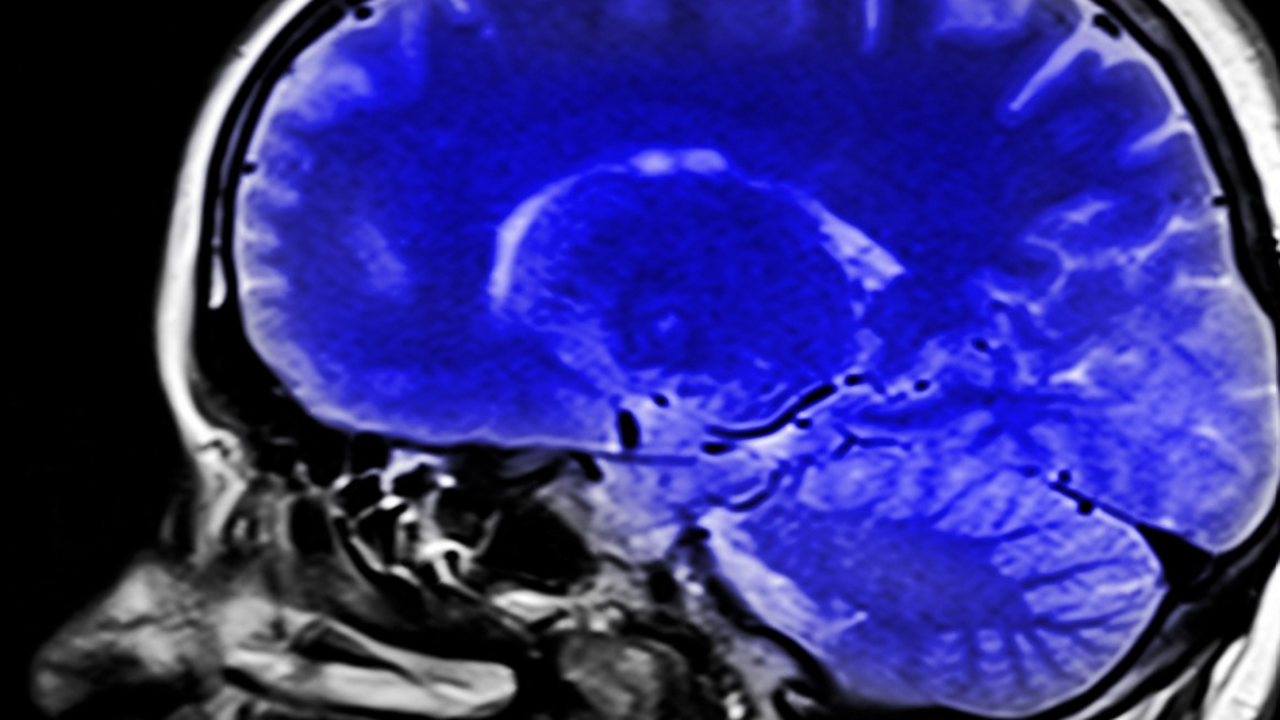

Учёные из Университетского колледжа Лондона пришли к выводу, что нарушения памяти при болезни Альцгеймера могут быть связаны не с исчезновением механизма запоминания, а с его неправильной работой. Исследование, проведённое на лабораторных мышах, показало, что ключевую роль играет сбой в процессе так называемого «повторного воспроизведения» недавних событий мозгом в состоянии покоя.

В норме этот процесс происходит в гиппокампе и помогает закреплять воспоминания: группы нейронов, отвечающих за ориентацию в пространстве, активируются в определённой последовательности, отражая ранее пережитые события. Однако у мышей с амилоидными бляшками, характерными для болезни Альцгеймера, учёные зафиксировали серьёзные нарушения. Хотя сами события воспроизведения происходили с обычной частотой, их структура была дезорганизована — нейроны «перемешивались» и теряли чёткую последовательность активации.